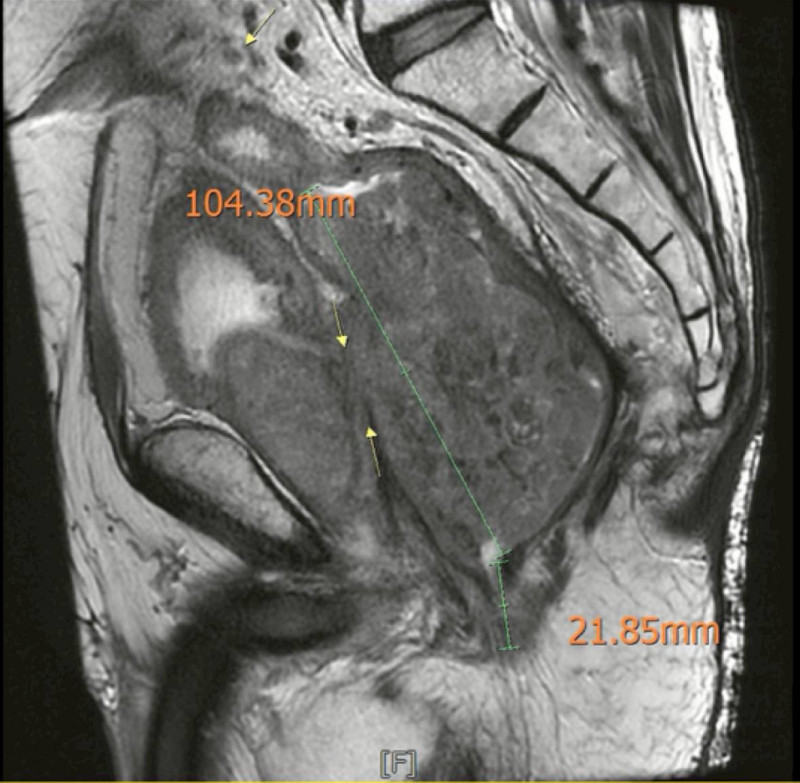

〔記者蔡淑媛/台中報導〕61歲的王先生一年前確診罹患巨大局部晚期直腸癌,腫瘤已侵犯到泌尿系統,腫瘤一度破裂引發致命性的會陰部壞死性筋膜炎,中國醫藥大學附設醫院直腸外科醫師黃晟瑋評估後先為他進行抗生素治療、感染控制、營養支持,體力恢復後接受「骨盆複雜腫瘤根除手術」,重建永久性人工肛門與泌尿造口,成功清除腫瘤,生活也恢復自理。

王男的巨大直腸癌腫瘤有10公分,腫瘤破裂引發會陰部壞死性筋膜炎,緊急清創與感染治療後,接受放化療,腫瘤局部縮小,但因體力支撐不住,一直未手術切除腫瘤,僅口服化療及保守治療,身體每況愈下,反覆泌尿道感染、發燒、虛弱與營養不良。

王先生接受骨盆複雜腫瘤根除手術,包括全直腸與肛門、膀胱與攝護腺切除,以及骨盆腔淋巴結清除、部分薦骨神經切除、會陰部受侵犯軟組織廣泛切除 ,並且建立永久人工肛門與泌尿造口,整形外科也為他進皮瓣重建會陰部傷口,手術龐大且複雜,手術順利完成。